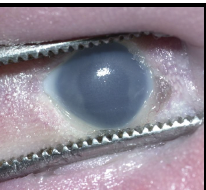

blue sclera